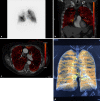

Background: Endoscopic lung volume reduction (ELVR) using one-way endobronchial valves is a technique to reduce hyperinflation in patients with severe emphysema by inducing collapse of a severely destroyed pulmonary lobe. Patient selection is mainly based on evaluation of emphysema severity on high-resolution computed tomography and evaluation of lung perfusion with perfusion scintigraphy. Dual-energy contrast-enhanced CT scans may be useful for perfusion assessment in emphysema but has not been compared against perfusion scintigraphy.

Material and methods: Forty consecutive patients with severe emphysema, who were screened for ELVR, were included. Perfusion was assessed with 99mTc perfusion scintigraphy and using the iodine map calculated from the dual-energy contrast-enhanced CT scans. Perfusion distribution was calculated as usually for the upper, middle, and lower thirds of both lungs with the planar technique and the iodine overlay.

Results: Perfusion distribution between the right and left lung showed good correlation (r = 0.8). The limits of agreement of the mean absolute difference in percentage perfusion per region of interest were 0.75-5.6%. The upper lobes showed more severe perfusion reduction than the lower lobes. Mean difference in measured pulmonary perfusion ranged from -2.8% to 2.3%. Lower limit of agreement ranged from -8.9% to 4.6% and upper limit was 3.3-10.0%.

Conclusion: Quantification of perfusion distribution using planar 99mTc perfusion scintigraphy and iodine overlays calculated from dual-energy contrast-enhanced CTs correlates well with acceptable variability.